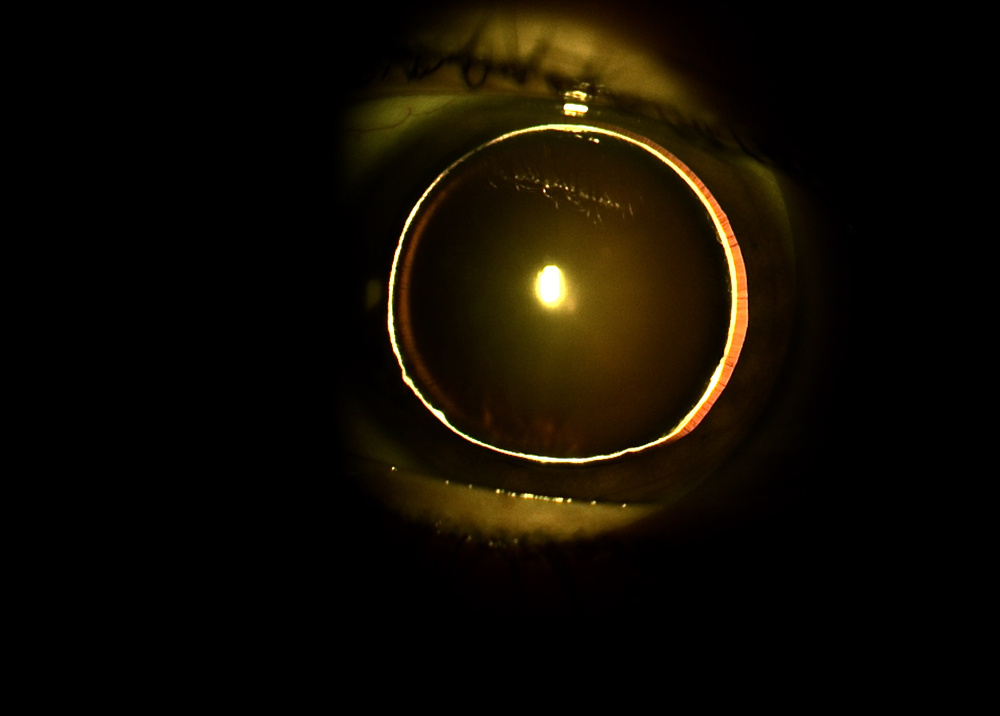

Título: Lunar lens & Eclipse of the Eye: The Dual Faces of a Cataract

Autor: Sofia Oliveira Machado

Coautores: Paulo Freitas-da-Costa

Instituição: ULS São João

Descrição: Slit-lamp images of the left eye. On the left, a narrow slit beam highlights a mature cataract subluxated temporally. On the right, retroillumination demonstrates complete obstruction of the fundus reflex, consistent with the opacity's maturity and position.